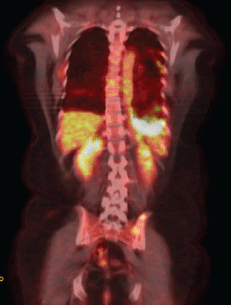

After four months of treatment, the patient was clinically well, with no new complaints. A new PET/CT was carried out, and it identified the permanence of the diffuse and nodular pleural thickening, predominantly at the base, but showing increased radiopharmaceutical uptake (SUV 17.7) (Figure 1b).

Figure 1b. PET–CT showing evidence of the presence of pleural thickening and increase of radiopharmaceutical capture.